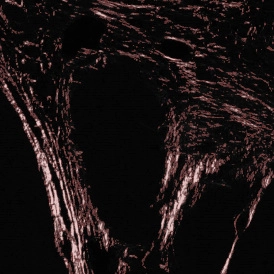

The IF Cytoskeleton App detects cytoskeletal structures based on a specific stain. The cell cytoplasm can be detected using other stains. Data can also be exported, including the number of cytoskeletal filaments inside and outside the cell and on the cell membrane, filament length, and total filament area.